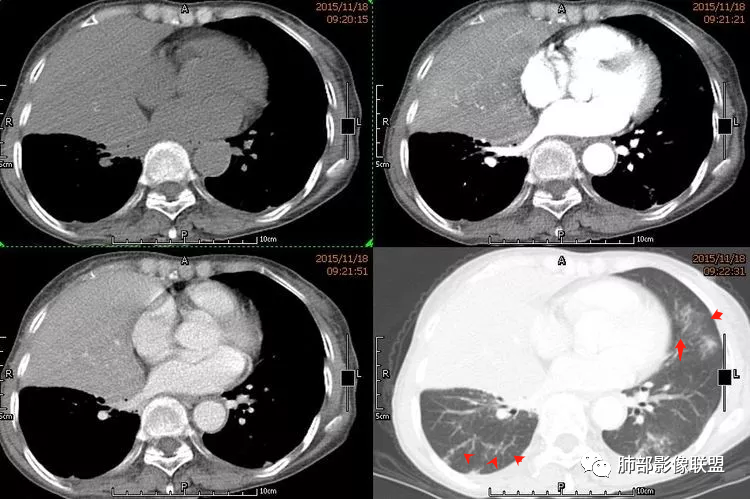

双肺多发大小不等结节,以胸膜下为主,部分边缘平直,彭隆,整体较密实,临床无症状体检发现,考虑淋巴瘤,转移瘤,IMT.

老年男性,发现占位半年,双肺多发结节,病灶边界清晰,浅分叶,部分支气管进入后堵塞,部分病灶内部密实,无增强,考虑真菌感染,淋巴瘤待排除。

双肺多发结节肿块,部分位于胸膜下,部分结节内可见扩张支气管,右肺上叶近肺门处结节呈分叶毛刺,支气管阻塞、扭曲扩张,考虑1淋巴瘤2腺癌转移。

双肺多发结节,密度均匀,部分可见支气管进去后堵塞,有胃部手术史,考虑淋巴瘤?鉴别腺癌转移,其他?

脾大表现,两肺叶多发结节,部分呈肿块(浅分叶轮廊),实性密度,边缘清楚,有膨隆,近胸膜下分布,支气管僵直略扩张,一元论,首选淋巴瘤。

双肺多发结节肿块,胸膜下支气管树旁为主,部分内可见支气管穿行,支气管扩张。淋巴瘤?肉芽肿性多血管炎?鉴别转移

必有路:老年男性,两肺多发结节,团块,病灶都位于胸膜下,血管相关,有支气管充气征,分叶,无坏死,周围无晕疾病谱:隐球菌病,GPA,OP,malt,转移,IgG4相关,栓塞诊断:鉴于患者体检发现半年,症状逍遥重点考虑 淋巴瘤 可能鉴别:隐球菌病,GPA,IgG4相关,转移

多发团块影,胸膜下为主,边缘清楚、膨隆、平直,部分病灶可见分叶,病灶内支气管穿行,血管穿行,考虑淋巴瘤。

刚看了视频,老年男性,体检发现,30年前有胃部手术史。双肺野多发结节肿块影,沿支气管血管束或胸膜下分布,有的结节内似有小空洞,支气管进入走形自然,肿块边缘膨隆,有分叶,支气管进入后有的截断,大部分支气管穿过,走形自然,纵隔内未见明显肿大淋巴结,总体考虑淋巴瘤,炎性肉芽肿(肉芽肿血管炎或隐球菌肺炎)等。考虑后者可能性大,肉芽肿血管炎或隐球菌肺炎,鉴别淋巴瘤。

病变分布特点,胸膜下,叶间胸膜下为主,呈大小不等结节级团块影,部分病灶内见支气管影,病灶收缩不明显,从分布及慢性发病看,隐球和淋巴瘤都可,补充增强,病灶内见血管穿行,强化不明显,支持淋巴瘤

老年男性,两肺多发结节肿块,胸膜下分布为主,部分支气管进入闭塞,增强扫描有强化,血管穿行无破坏,边缘尚光滑,周围无晕,病灶整体膨隆为主,半年病程,症状逍遥,首先考虑淋巴瘤

棉花糖:双肺多大小不等结节,边缘清楚,无毛刺,浅分叶,胸膜下分布为主,内可见支气管穿行,增强后中等程度强化,病灶内血管走行自然,考虑淋巴瘤,鉴别GPA